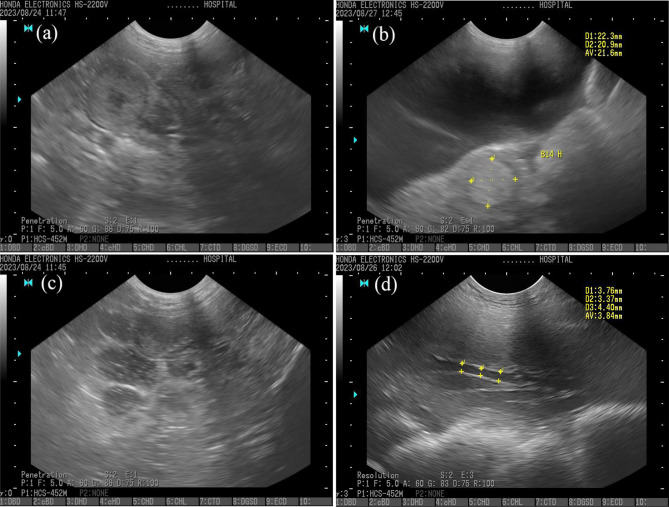

Results: Fourteen Landrace × Yorkshire sows were included in the study. Uterine diameter and uterine vessel size were measured from 2 to 15 days postpartum using B-mode ultrasonography, a non-invasive technique that enables continuous monitoring of uterine involution and detection of reproductive problems in the same sows throughout the 15-day postpartum period. To determine the relationship between farrowing duration and uterine diameter, sows were categorized into two groups: sows with a farrowing duration of ≤ 300 min (normal) and sows with a farrowing duration > 300 min (prolonged). The mean farrowing duration was 200 ± 128 min, with 28.6% of sows experiencing prolonged farrowing. In the prolonged farrowing group, the diameter decreased from 43.5 ± 9.4 mm to 12.4 ± 0.5 mm, while in the normal group, it decreased from 30.7 ± 1.4 mm to 13.6 ± 0.4 mm. On day 2, sows in the prolonged farrowing group exhibited a higher uterine diameter than the normal group (P = 0.042). There was no significant difference in the size of the uterine blood vessels between the two groups (prolonged farrowing: 7.3 ± 1.3 mm to 2.5 ± 0.1 mm; normal farrowing 6.1 ± 0.7 mm to 2.7 ± 0.1 mm) (P = 0.397). However, the uterine diameter was correlated with the size of the uterine blood vessels in sows with either a normal farrowing duration (r = 0.705, P < 0.001) or a prolonged farrowing duration (r = 0.749, P < 0.001).